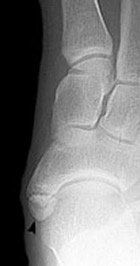

Acccessory navicular

In approximately 10% of the population there is an accessory navicular, or an extra navicular bone. Usually the accessory navicular is not large enough to cause symptoms.

Feet associated with the accessory navicular are usually flat footed, or excessively pronated. The accessory navicular can be prominent causing footwear irritation. The posterior tibial tendon can become overstretched causing degenerative tendinopathy, inflammation of the tendon sheath or irritation between the two fragments of the navicular.